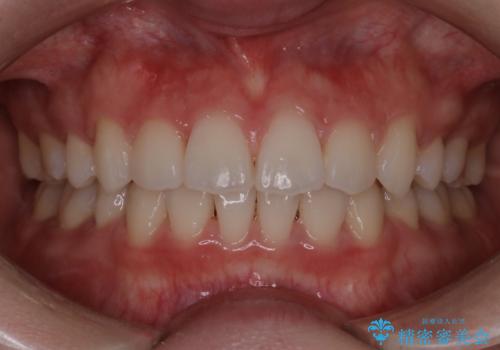

前歯の乱れをスッキリ解消!抜歯矯正で整えた美しい歯並び

担当医 河口智英